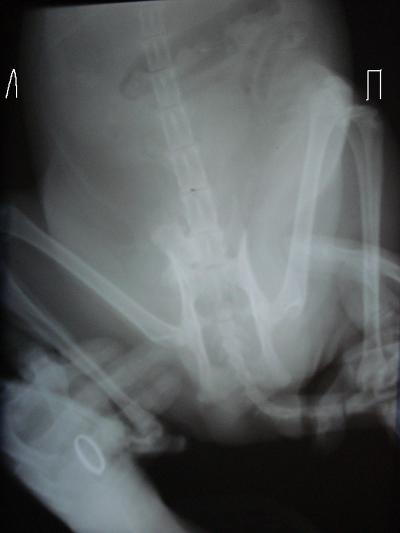

Наиболее частый симптом — хромота разной степени выраженности, от легкой (незначительная) до тяжелой, когда собака совсем не пользуется лапой (Рис. 3). Часто хромота периодическая на протяжении 1-2-х месяцев, а затем переходит в постоянную. Иногда можно заметить отек, припухлость или увеличение конечности в размере (Рис. 4). Также в редких случаях может произойти так называемый «патологический перелом» который происходит при незначительных нагрузках (на прогулке) и связан с разрушением большей части пораженной кости (Рис.

5).

Рис. 5. Компьютерная томограмма грудной конечности пациента с патологическим переломом на фоне остеосаркомы плечевой кости.

Прогноз в виде продолжительности жизни пациента зависит от стадии болезни, а это определяется наличием или отсутствием отдаленных метастазов. Для более точной диагностики и выявления метастазов, альтернативной рентгеновским снимкам может быть компьютерная томография всего пациента с выполнением онкологического поиска (Рис.

Компьютерная томография грудных конечностей этого же пациента.

3D моделирование: Компьютерная томография грудных конечностей с сочетанной КТ-биопсией кости.